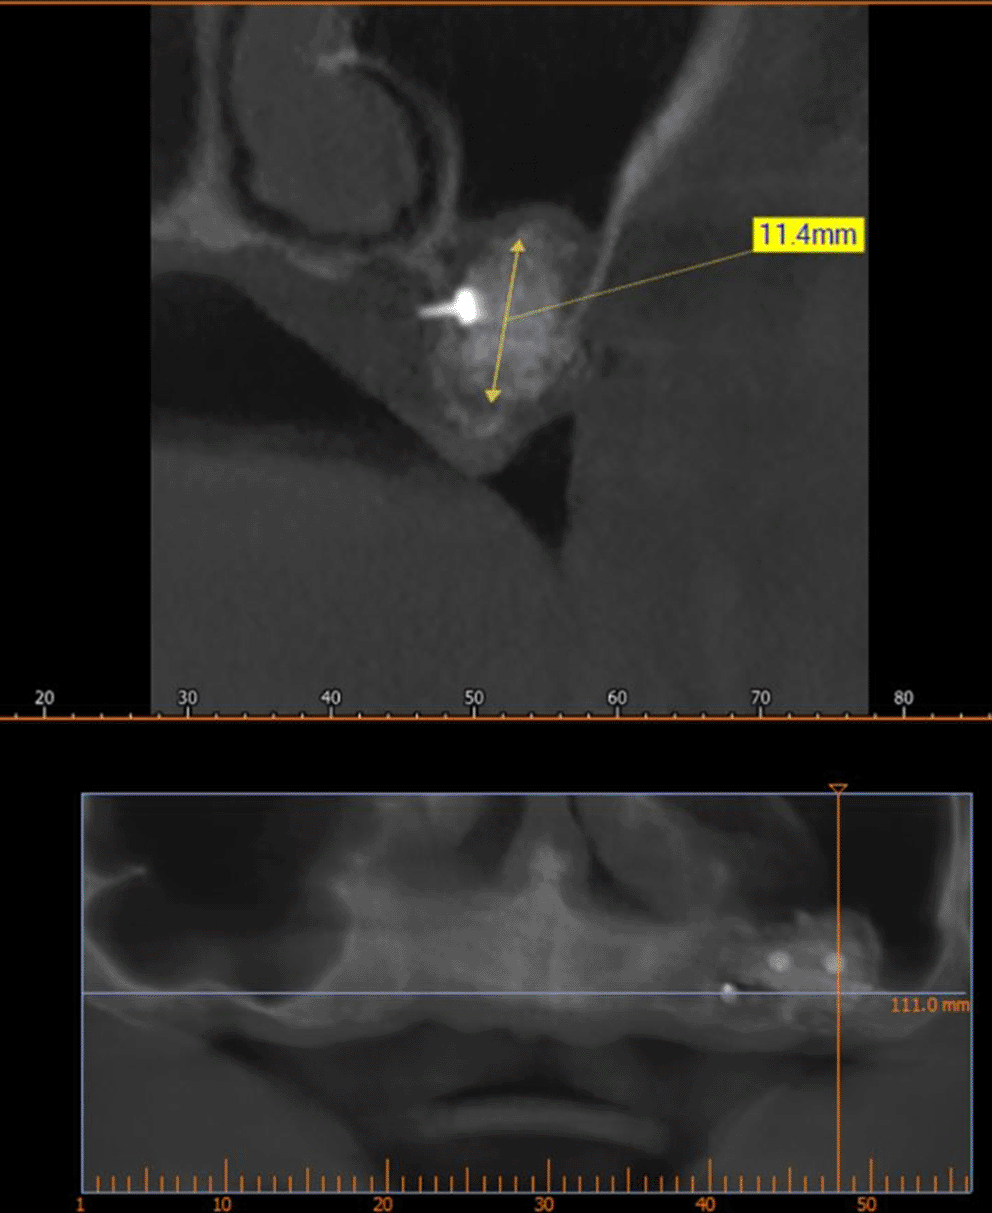

After implant planning using the cone-beam computed tomography CBCT, it was found that the alveolar bone height corresponding to the maxillary sinus floor was (0.5-1 mm) ( Figure 1), which indicates an external sinus lift.

3928750d-b091-43c3-94bb-6b181f3845d3_figure1.gif

Figure 1. CBCT shows the thickness of the maxillary sinus floor.

A CBCT scan was performed immediately after grafting and showed a direct bone gain of (11.4 mm) ( Figure 10) and 9 months after bone grafting where subsequent bone gain (11.4 mm) was found ( Figure 11).

3928750d-b091-43c3-94bb-6b181f3845d3_figure10.gif

Figure 10. CBCT after grafting immediately.